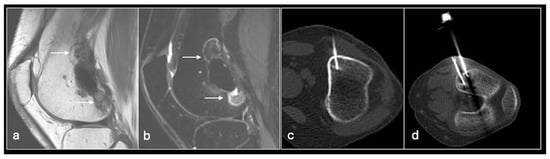

Figure 2. Axial T2fat suppressed (a), sagittal Proton density (b) showing tumour in the distal femur. Axial CT (c) showing biopsy needle in the distal femoral lesion.

We use two main needle systems. Most bone lesions can be sampled with a T-Lok eight-gauge system with an inner diamond-tipped stylet and outer cannula. This is inserted through the cortex overlying a bone lesion. Once in the lesion, the stylet is removed and the cannula is advanced to the deep wall of the lesion aiming to trap the core against normal bone on either side. A tray is then inserted through the cannula to acquire the sample. Both tray and cannula are withdrawn together and the sample is then deposited into the relevant histopathology or microbiology pots (Figure 2 and Figure 3). Typically, only one sample is needed unlike in a soft tissue biopsy.